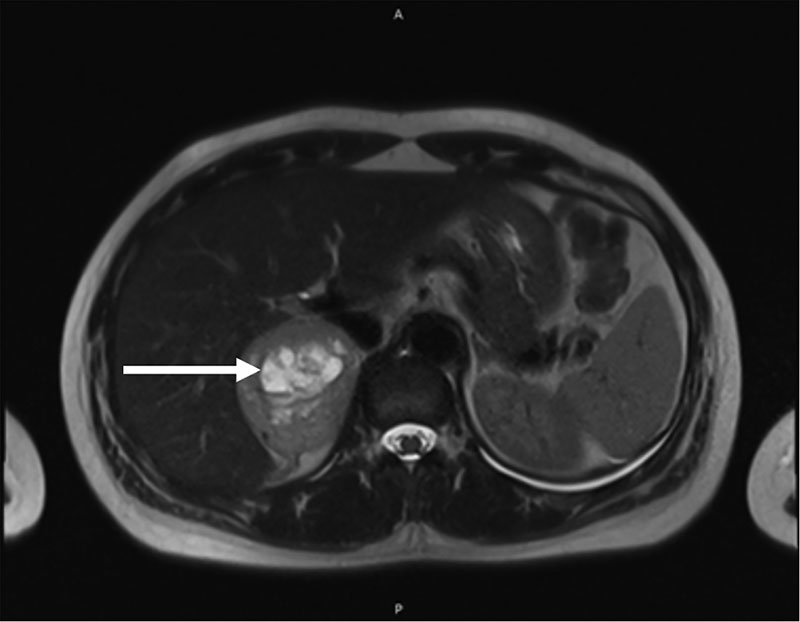

Рис. 1. Образование правого надпочечника на компьютерной томограмме в аксиальной плоскости, указано стрелкой

По данным компьютерной томографии (КТ) ОБП и забрюшинного пространства от 11.12.2024 г.: надпочечники – левый Y-образной формы, образований не выявлено; правый содержит образование, неравномерно накапливающее контрастное вещество, 63 × 53 мм. После внутривенного усиления накопление контрастного вещества в нативную, артериальную, венозную, отсроченную фазы составляло 29/56/52/47 HU (единиц по шкале Хаунсфилда) соответственно.

Заключение: КТ-признаки кистозно-солидного образования правого надпочечника, мелких кист печени, желчнокаменной болезни (ЖКБ), хронического холецистита; двусторонний минимальный гидроторакс (рис. 1, 2).